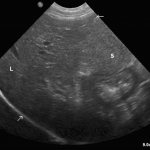

Asimismo, tenemos equipos de diagnóstico médico-veterinario para que usted y su mascota puedan beneficiarse sin salir de casa.